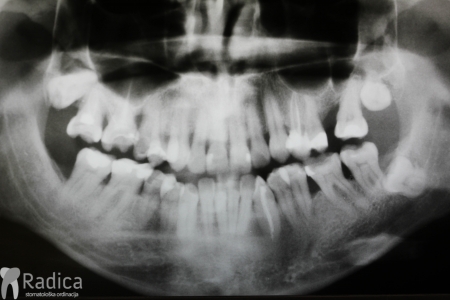

U ovom slućaju 28 godina star pacijent je zatražio ortodontsku terapiju. Na pregledu je uočen perzistentni donji desni mliječni očnjak a ortopan je potvrdio postojanje impaktiranog trajnog nasljednika. Tijekom terapije je uočeno oštećenje korijena desnog lateralnog sjekutića koji je izvađen a na njegovo mjesto je postavljne očnjak i preoblikovan ljuskicom.